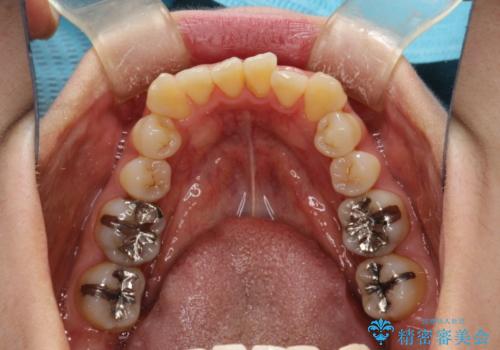

矯正治療が始まる前に歯のお掃除

- これから矯正治療を始めるため、今の状態でも歯をきれいにしておきたいとのことでした。PMTC60分コースを行いました。

プラーク(細菌の塊)や歯石がたまると歯の表面はザラつきいてきます。そのザラつきは歯周病や虫歯菌の棲家となります。そのまま放置すると、歯肉が腫れてきたり、歯肉から出血したり、口臭が強くでたりします。とくに歯肉の境目は、歯磨きで汚れを除去することが難しく、プラーク(細菌の塊)や歯石が溜まりやすい場所です。

歯並が、がたついている場合はなおさら汚れが溜まりやすいです。矯正治療前や矯正中、定期的にPMTCをすることで、矯正治療中の歯肉トラブルを防ぐことにつながります。